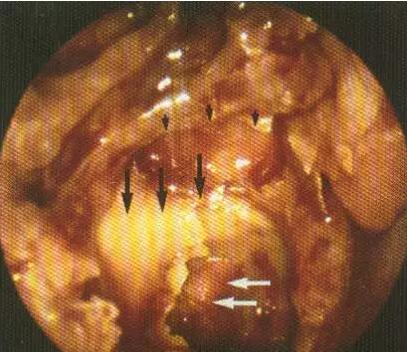

蝶窦外侧壁(黑箭头:视神经管 白箭头:颈内动脉 小黑箭头:蝶窦前壁缘)

蝶窦与颈内动脉

多数颈内动脉在蝶窦内形成一条自后向前凸向窦内的隆起

隆起骨壁很薄(1mm左右)

隆起骨壁可有自然缺损(8-4%)

蝶窦内颈内动脉隆起的特点

出现率:55-77%

多数为压迹型:高度:0.20--3.45mm

厚度:0.15--4.10mm

半数以上的高度和厚度均小于 1mm。

颈内动脉各段压迹出现率不同,鞍前段出现率最高、骨壁最薄。